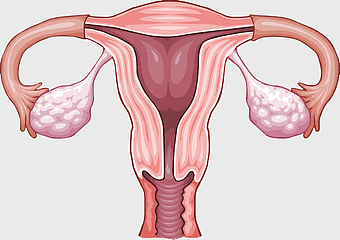

female reproductive anatomy, menstrual cycle illustration, ovarian health diagram, uterus and ovaries visual, gynecological health image, reproductive system education, human fertility chart -